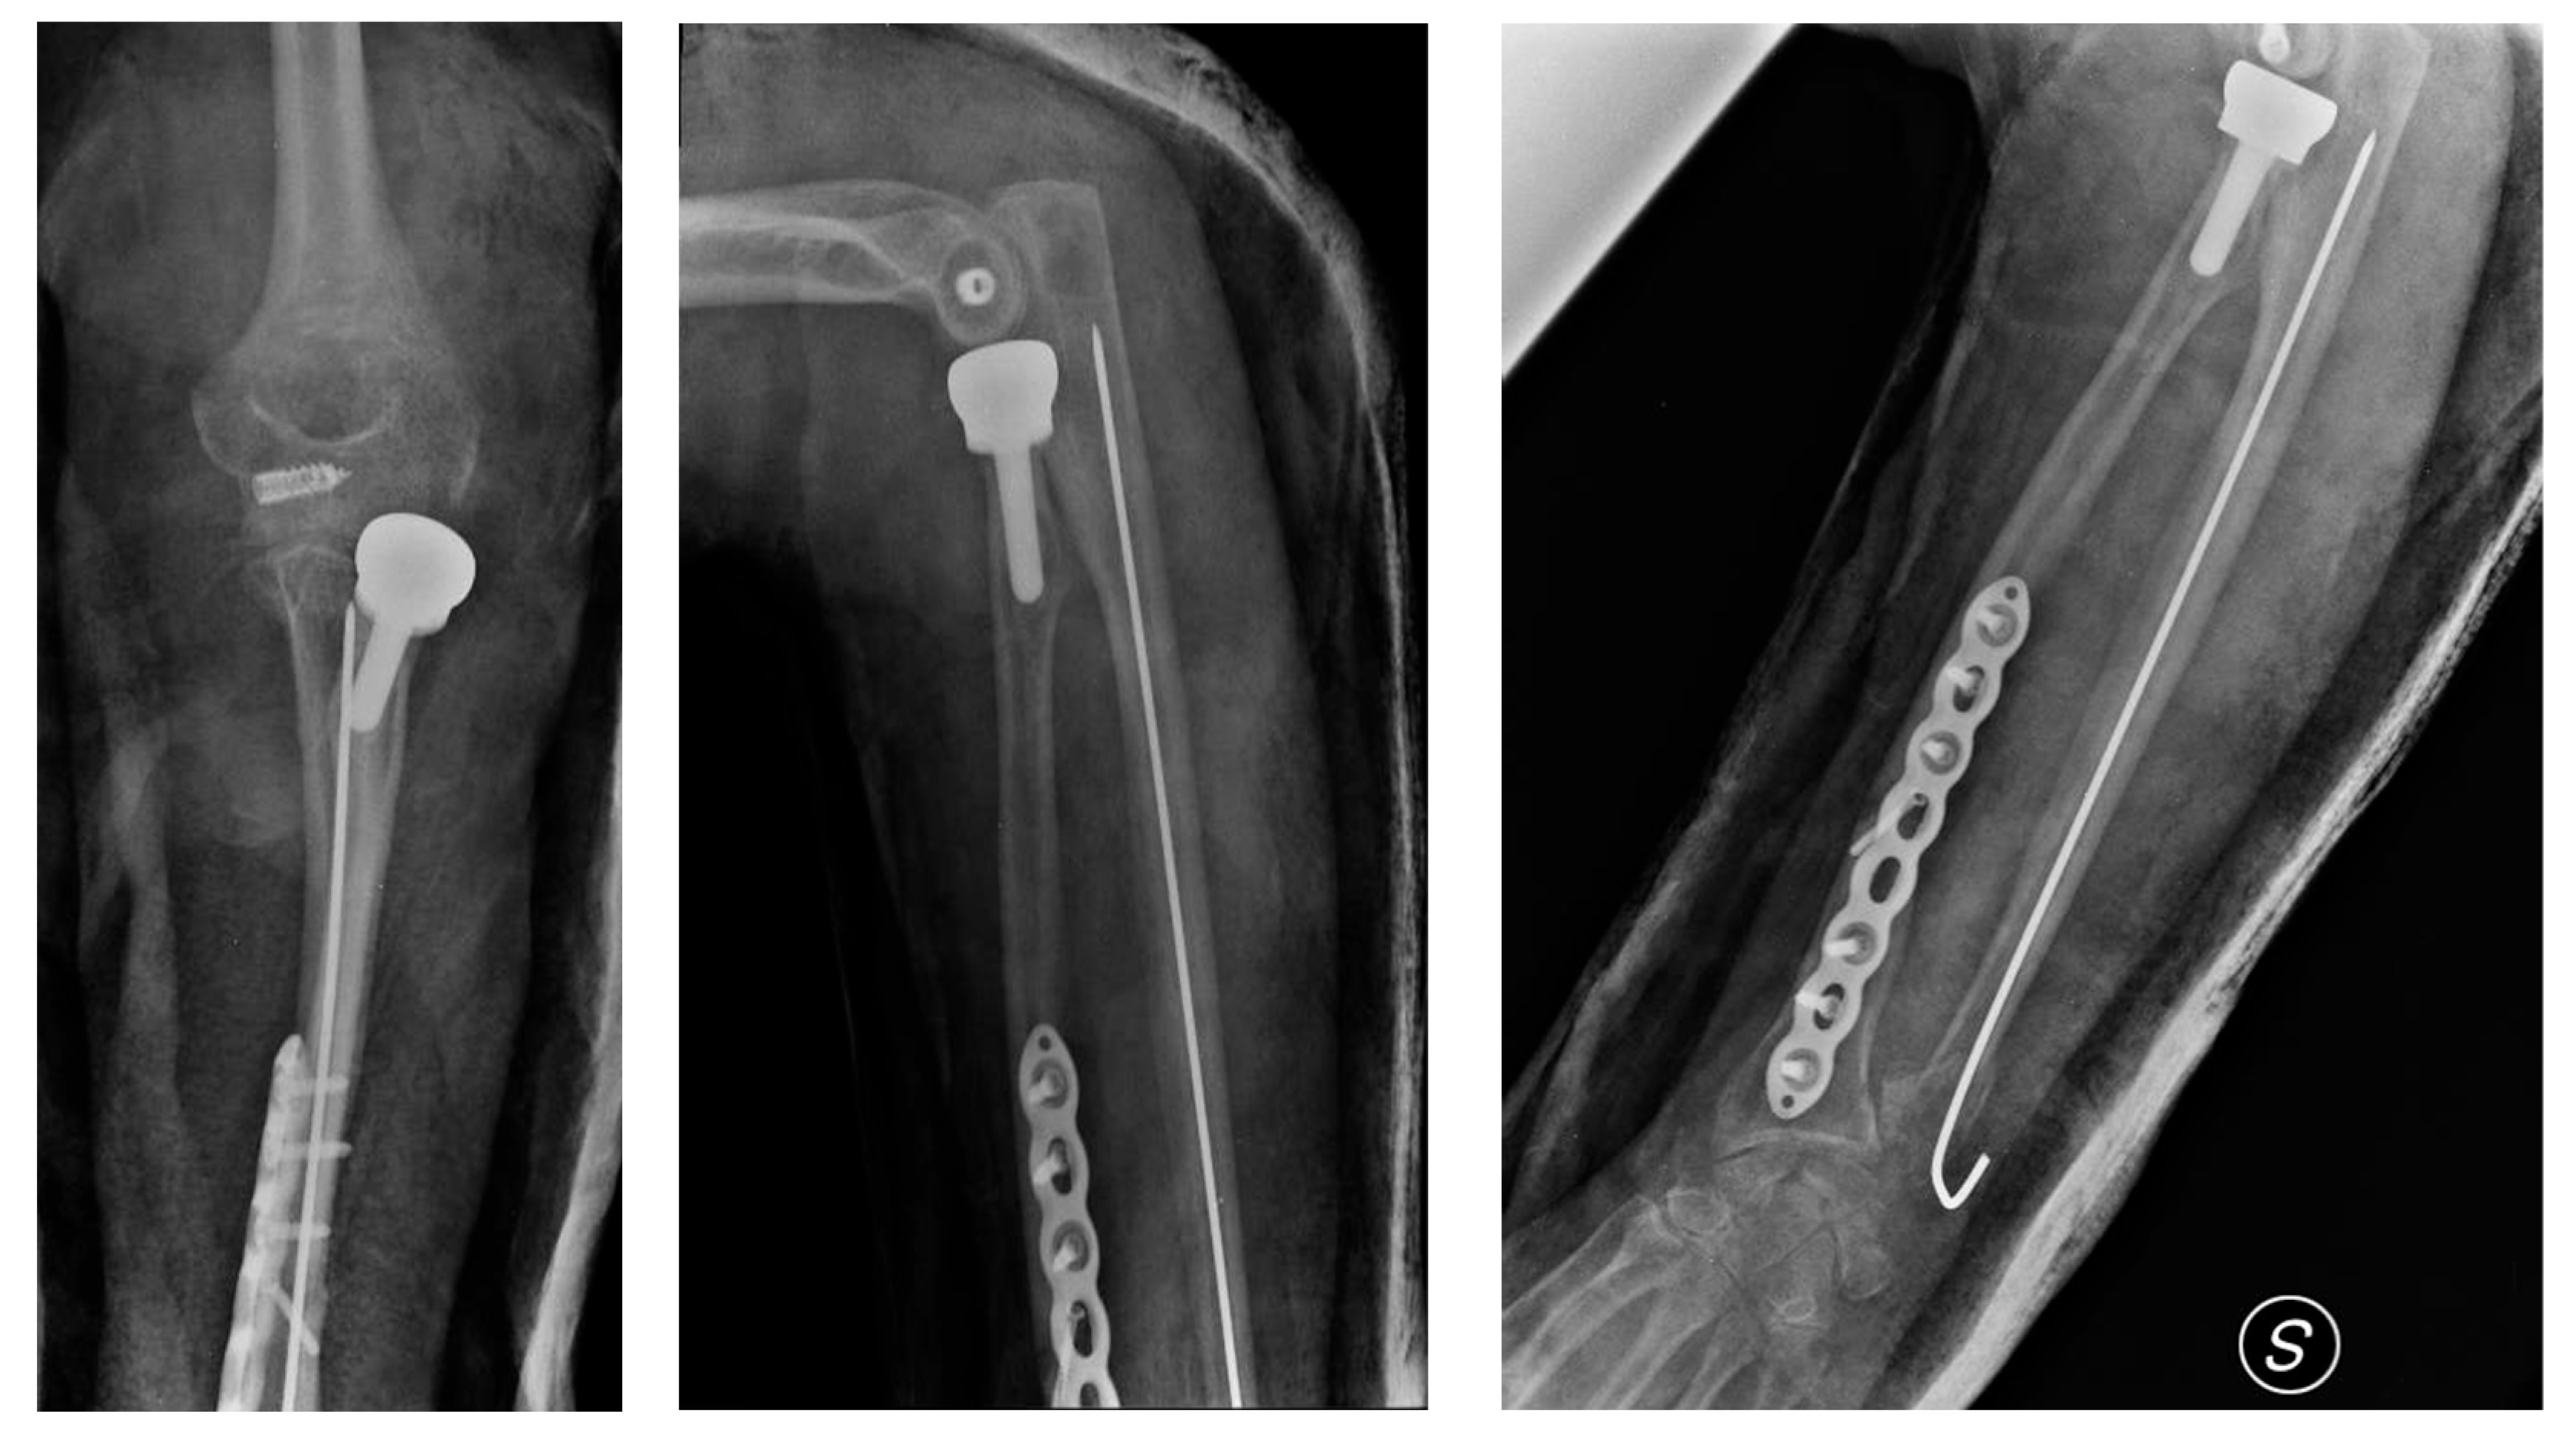

Upon physical examination, the patient exhibited a gross deformity of the left arm, with tenderness localized to the olecranon and wrist regions. The limb demonstrated complete functional impairment, with limited movement and significant swelling. Radiographic evaluation, including urgent X-rays, revealed a comminuted fracture of the distal third of the radius with dorsal displacement of the distal fragment and a comminuted fracture of the distal ulna metaphysis. Additionally, there was a multi-fragmentary radial head fracture, accompanied by partial detachment of the articular head, which raised concern for significant instability (Figure 1 and Figure 2). Based on these findings, a diagnosis of complex forearm fracture/dislocation with suspected longitudinal instability was made.

Figure 2. CT-based 3D model performed at the emergency room entrance.